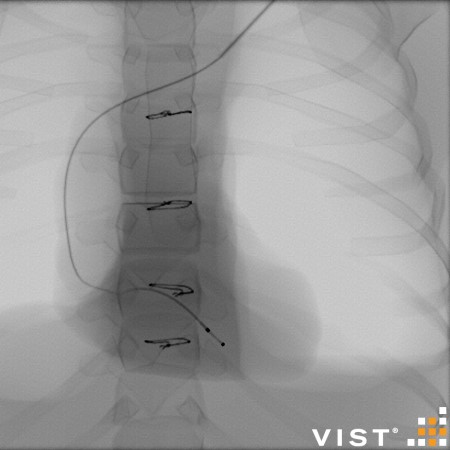

Simuladores Endovanculares.

módulos内血管分发

Aquíhayuna listademódulosundonibles concatibles con el simulador vist g5(Versiónforporidenteyy lab,没有兼容的孔血管y vist灯)。Esta listaestántancoreeevolución,没有Dude en advertarla promicy ... los dutallesestándisponibles haciendo clic en eltítulodelmódulo(网站蒙黛尔,enInglés)